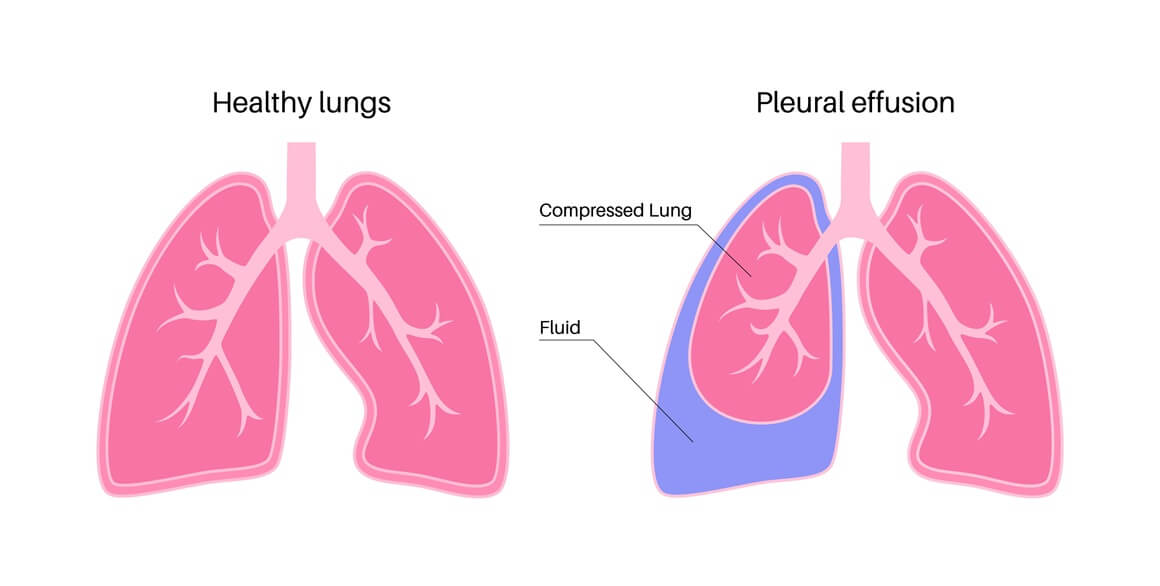

Voda u plućima ili pleuralni izljev (pleuralni izljev pluća) prekomjerno je nakupljanje tekućine u pleuralnom prostoru, odnosno u prostoru između dvije poplućnice.

Kada udahnemo, naš se prsni koš širi, a dijafragma (ošit) spušta. Kada izdišemo, dijafragma se podiže, a prsni koš sužava. Kako bi se to moglo dogoditi, pluća i rebra omeđuje tanak sloj tekućine koji djeluje kao lubrikant.

Problem nastaje kad se taj prostor prekomjerno ispuni tekućinom zbog niza uzroka. To se naziva pleuralnim izljevom ili nakupljanjem vode u plućima (potrebno razlikovati od plućnog edema!). Tekućina koja ispunjava pleuralni prostor može biti:

Pleuralni izljev pluća može biti lokaliziran samo na jednu stranu, pa razlikujemo pleuralni izljev desno i pleuralni izljev lijevo, dok se pleuralni izljev kod djece javlja puno rjeđe.